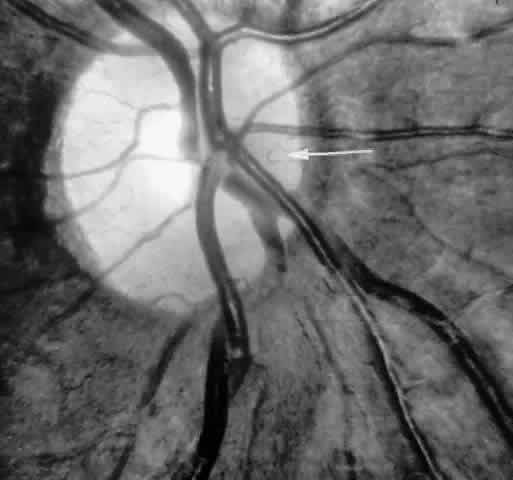

Angioid Streaks

Angioid streaks occur in association with sickle cell disease, with an overall incidence of less than 6%.72–75 The changes are more common in patients with homozygous sickle cell anemia and are age-dependent, occurring in 2% of sickle cell anemia patients less than 40 years of age versus 22% in those who are more than 40 years of age (Fig. 5).76

Fig. 5. A 45-year-old man with homozygous sickle cell anemia and angioid streaks (arrows).

Unlike the angioid streaks seen in patients with pseudoxanthoma elasticum, choroidal neovascularization and disciform disease are uncommon in association with sickle cell disease. Elastic tissue degeneration, as is seen in pseudoxanthoma elasticum, has not been demonstrated in the skin biopsy specimens of sickle hemoglobinopathy patients with angioid streaks.73,75 Initially, the etiology of angioid streaks in sickle cell disease was hypothesized to be secondary to iron deposition due to chronic hemolysis, causing brittleness of Bruch's membrane. Histopathologic examination of angioid streaks in a patient with homozygous sickle cell anemia, however, revealed heavy calcification of Bruch's membrane without evidence of iron or hemosiderin.77